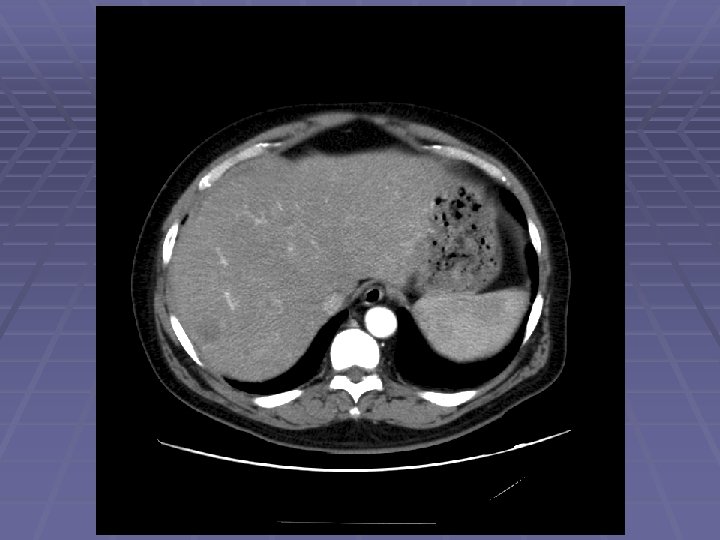

Hyperechoic Liver Masses

FNA of Hyperechoic Liver Mass

EUS Evaluation of Left Lobe of Liver